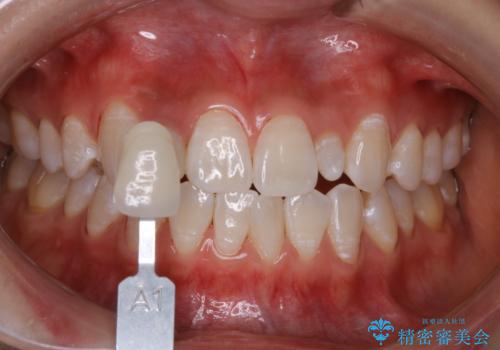

前歯のセラミックを作る前にホワイトニング

- 前歯のセラミッククラウンの型取りの前に、ホワイトニングで全体を白くしたいとのことでした。オフィスホワイトニングのエクセレントコース・トリートメントを行いました。

- 33,000円(税込)費用は治療当時の料金となります